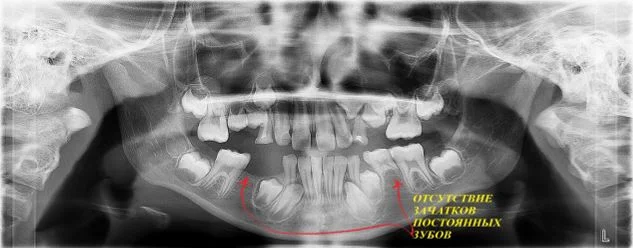

В детской стоматологии обойтись без рентгена невозможно. Под корнями молочных зубов располагаются зачатки постоянных зубов, и прежде чем начинать их лечение, необходимо убедиться, что корни молочных зубов не начали рассасываться, и что проводимое лечение не повредит зачаткам постоянных зубов.

Панорамный снимок - это не то, на чем можно сэкономить. Малейшая ошибка в диагностике при отсутствии снимка - это риск серьезных упущений в лечении и дополнительных затрат.